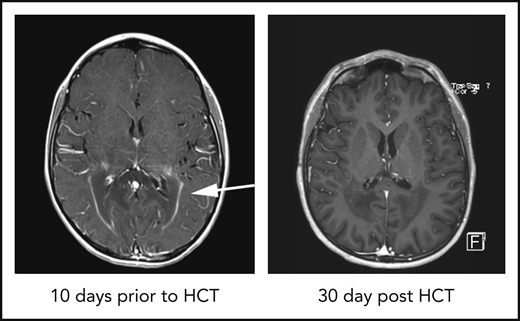

Gadolinium resolution on brain MRI correlates with donor neutrophil recovery in cALD patients. (A) Example of a T1-weighted MRI showing a classic ring of gadolinium contrast (arrow; left panel). An MRI exhibiting complete gadolinium contrast resolution 30 days after HCT (right panel). (B) Percentage of patients having complete gadolinium resolution at the indicated time points after HCT. The blue columns represent patients with neutrophil recovery and single HCT, and the red columns represent patients who failed to engraft. (C) Day of neutrophil recovery for patients with contrast resolution at the indicated cumulative time points post-HCT. (D) Frequency of contrast resolution between patients who had ANC recovery ≤ 16 days (faster) vs >16 days (slower). (E) Frequency of contrast resolution in cALD patients with higher CD15 chimerism (70-100%) vs lower CD15 chimerism (<70%) at 60 days post-HCT. (F) Table of pre-HCT and HCT parameters with univariate analysis P values. Variables used in the multivariate analysis model are in bold type. All P values were derived using Fisher’s exact test.

Adrenoleukodystrophy (ALD) is a rare X-linked peroxisomal disorder caused by mutations within the ABCD1 gene resulting in the accumulation of very long chain fatty within tissues, particularly the adrenal glands, testes, and the central nervous system (CNS).1 Most boys develop adrenal dysfunction at ages 4 to 7 years, and up to 40% of boys develop a severe demyelinating form of ALD, cerebral ALD (cALD), between ages 4 and 10 years (median 7 years).1 cALD is progressive, neurologically devastating, and fatal without intervention. The hallmarks of cALD disease manifestation are regions of demyelination observed on brain magnetic resonance imaging (MRI) that are associated with a “garland ring” of gadolinium contrast enhancement, often localized to the occipital–parietal region. Gadolinium enhancement indicates active blood-brain barrier (BBB) disruption.2 Only hematopoietic cell transplant (HCT) has been shown to halt neurologic progression, with the best outcomes when HCT is performed early in the disease process, although the mechanism of disease arrest by donor hematopoietic cells is unknown.3 Following HCT, the gadolinium enhancement resolves as soon as 28 days after transplant in some patients (Figure 1A), and it is thought that most patients will show gadolinium resolution by 100 days after HCT, indicating elimination of active neuroinflammation. The factors associated with gadolinium resolution are not known. Our goal was to evaluate gadolinium resolution in boys undergoing HCT for cALD and determine whether there were other biomarkers of disease or transplant characteristics that were associated with resolution.